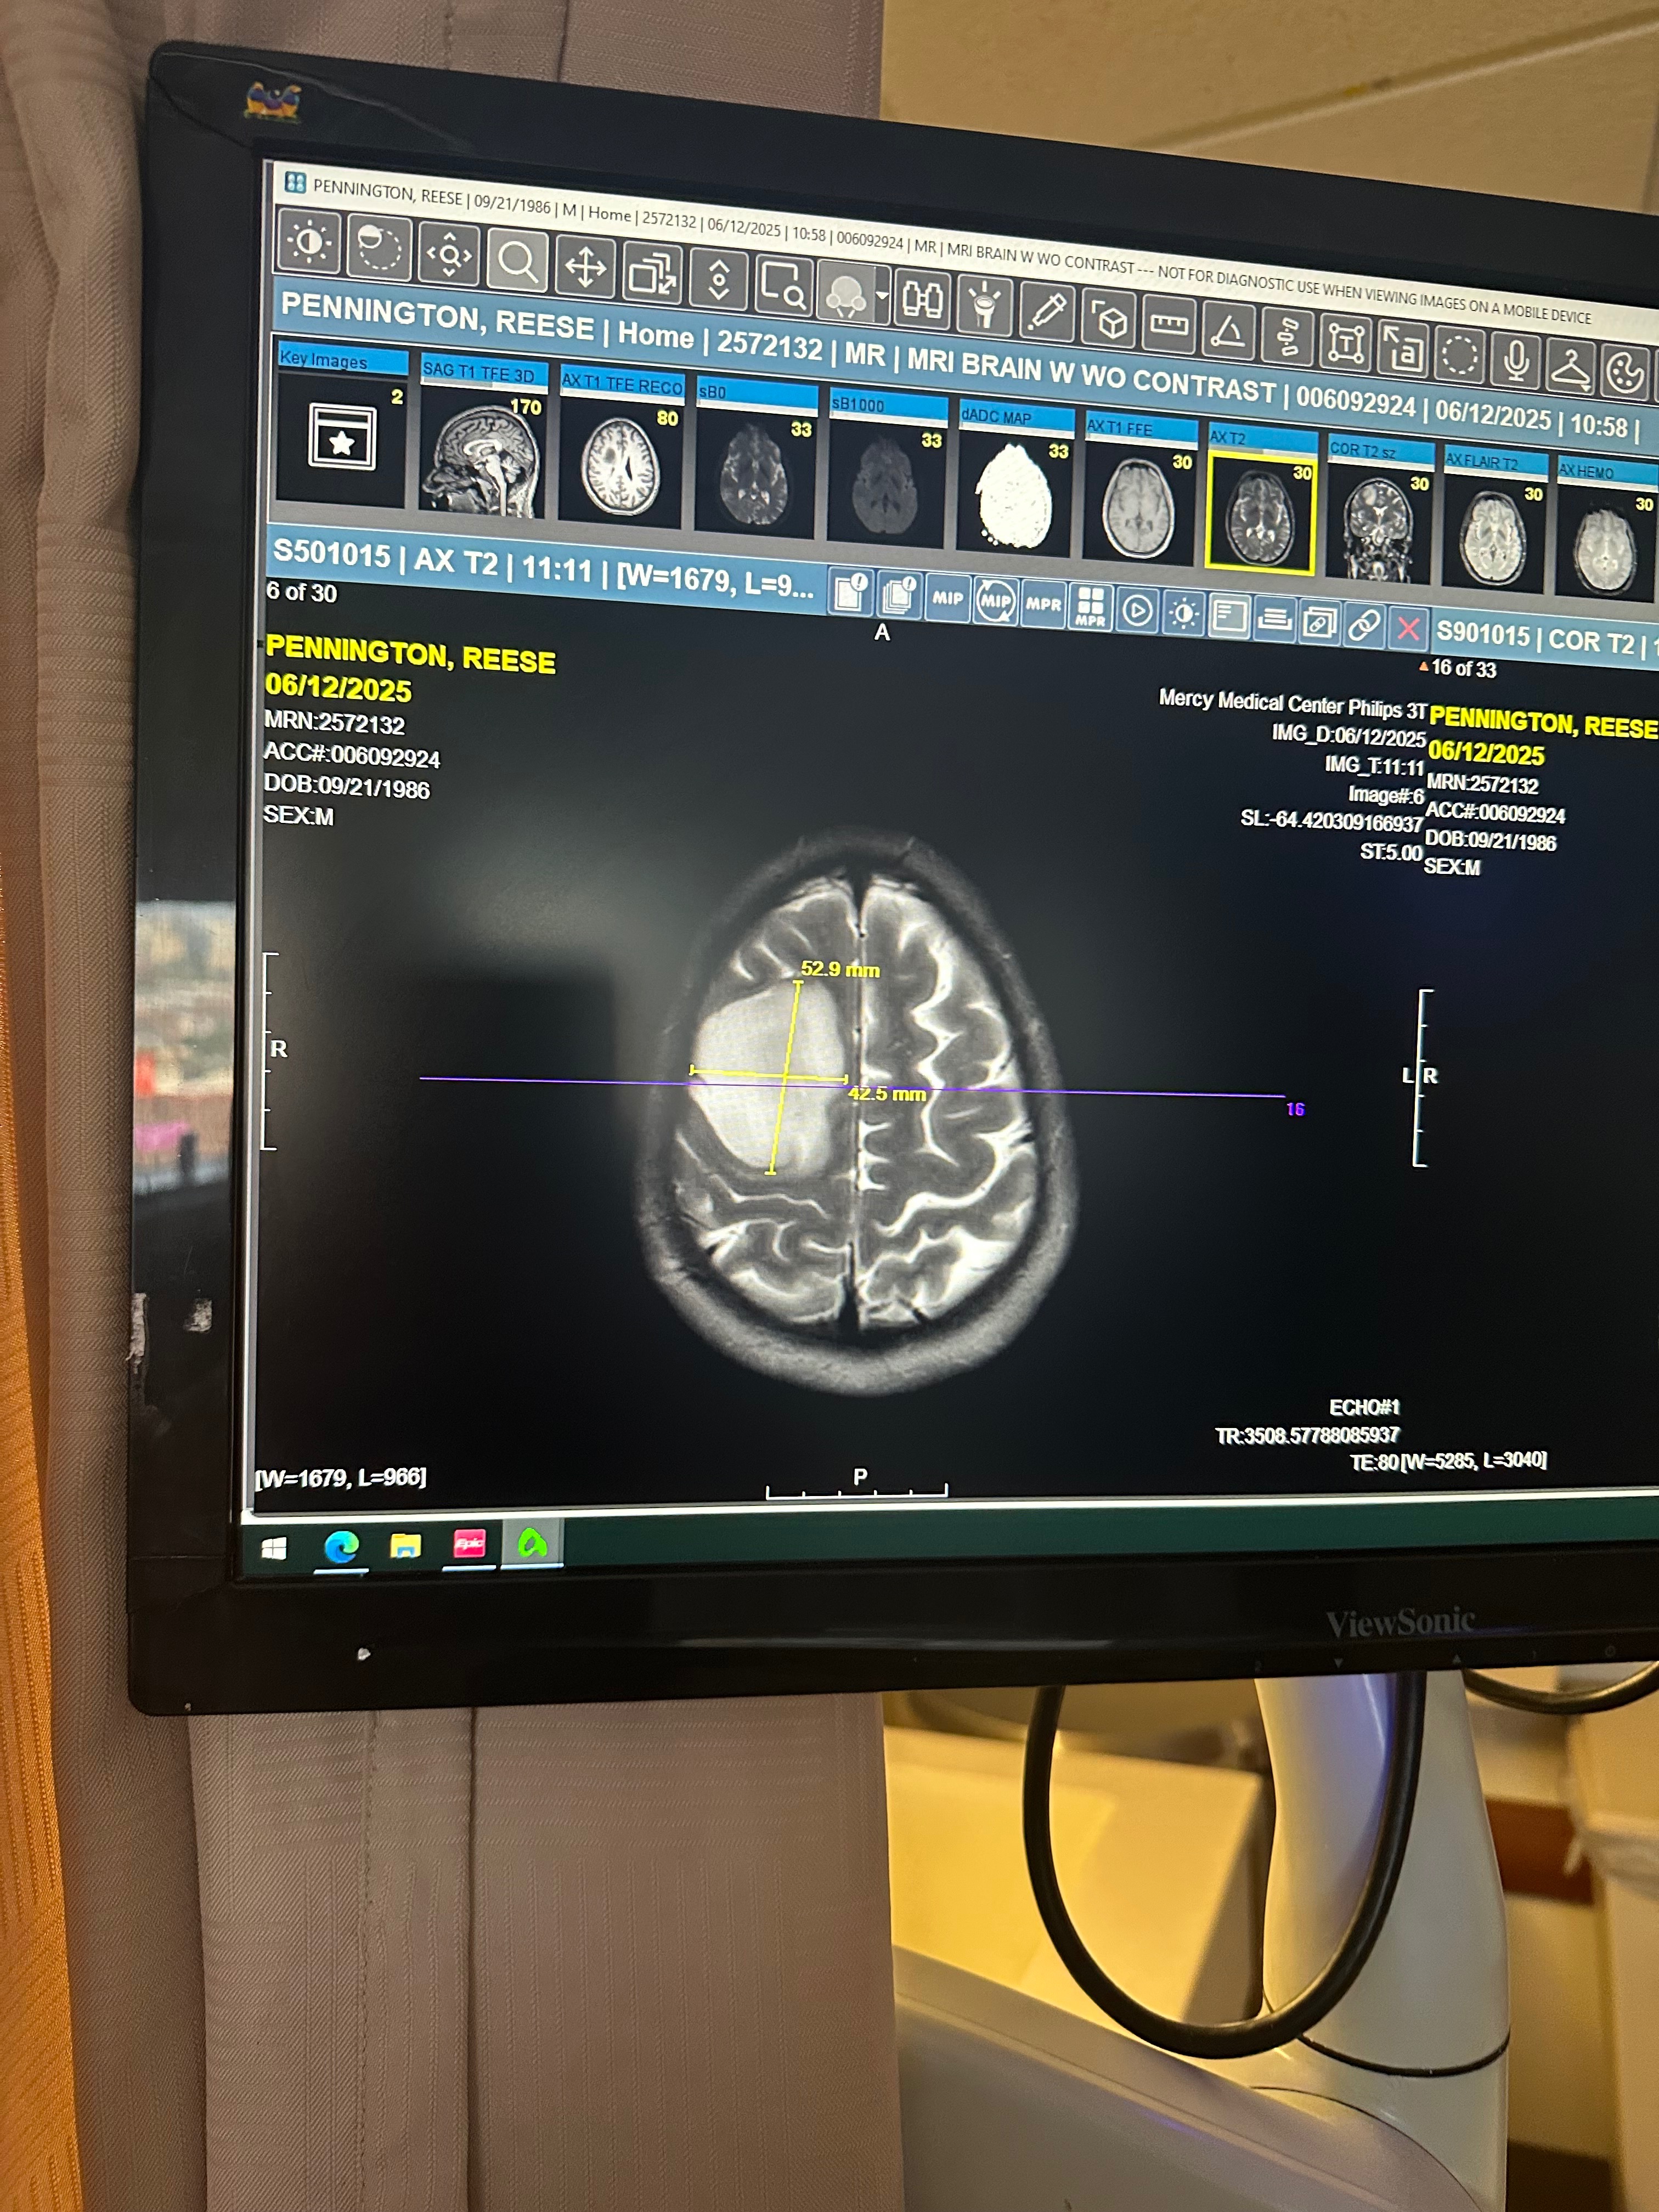

Reese was recently diagnosed with a Grade 2 Oligodendroglioma — a rare, slow-growing but serious primary brain tumor. It’s something no one ever expects to hear, especially at just 38 years old.